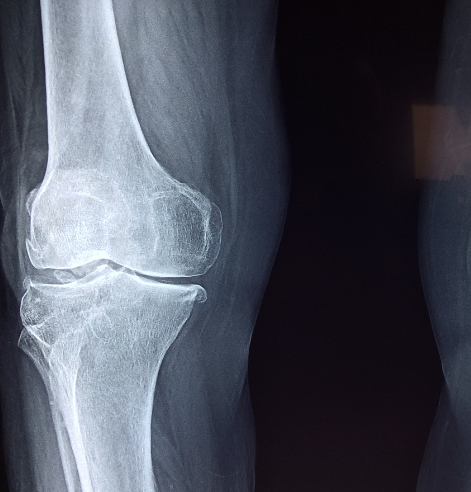

뼈는 우리 몸의 구조를 지탱하고 활동을 가능케 하기 위한 중요한 요소입니다. 그러나 노화나 여러 요인으로 인해 뼈의 밀도가 감소하고 취약해질 수 있습니다. 이러한 상태를 골다공증이라고 합니다. 골다공증은 뼈의 조직 변화로 인해 부러질 위험이 높아지는 만성적인 질환으로 특히 여성들에게 더 많이 발생합니다. 그러나 골다공증에 좋은 음식과 올바른 영양소 섭취로 뼈 건강을 지키고 칼슘, 비타민 D, 마그네슘 등이 풍부한 음식을 소비함으로써 골다공증을 예방하고 개선할 수 있습니다. 이 글에서는 골다공증 예방에 도움이 되는 골다공증에 좋은 음식에 대해 자세히 살펴보겠습니다.

골다공증은 뼈 건강에 영향을 미치는 중요한 질병 중 하나입니다. 노화와 함께 발생하는 이 질병은 뼈의 밀도 감소로 인해 부러질 위험이 증가하며특히 여성들에게 주로 나타납니다. 골다공증에 좋은 음식을 섭취하는등 건강한 식습관과 올바른 영양소 적절한 운동은 골다공증을 예방하고 관리하는 데 핵심적입니다. 골다공증에 좋은 음식들을 다양하게 조합하여 균형 잡힌 식단을 구성하면 뼈 건강을 유지하고 골다공증 예방에 도움이 될 것입니다. 또한 식이 요구량은 개인의 건강 상태, 연령, 성별 등에 따라 다를 수 있으므로 전문가의 조언을 듣는 것이 좋습니다.